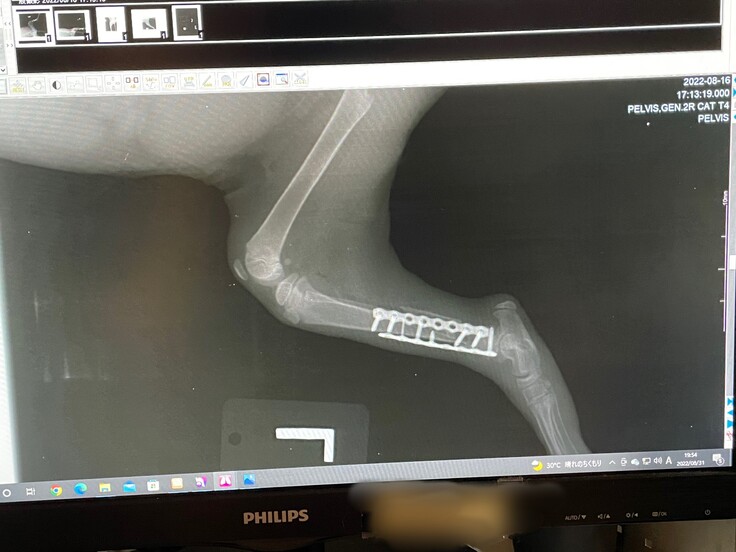

新着情報にも記載させていただきましたが、がおは1月19日に再手術が決まりました。

生後1か月ほどで手術を行ったため、脚を固定するボルトがうまく刺さっておらず、歩く邪魔になっており、撤去することになりました。

そのため、クラウドファンディング残りの期間で次回の手術代分をネクストゴールで目指していきたいと考えております。

金額としまして、第1ゴールの510,000円に、今回の手術代にREADYFORでの手数料12%を含めた85,000円をプラスし、合計595,000円を目指していきます。